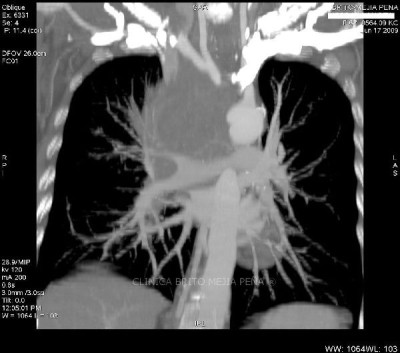

Trombosis arteria pulmonar coronal

Post Image